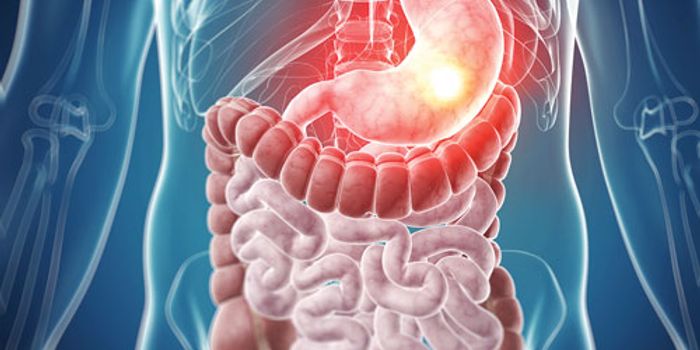

NOV 14, 2022ImmunologyThere are many types of microorganisms in the human gastrointestinal tract, and many of them perform important functions ...